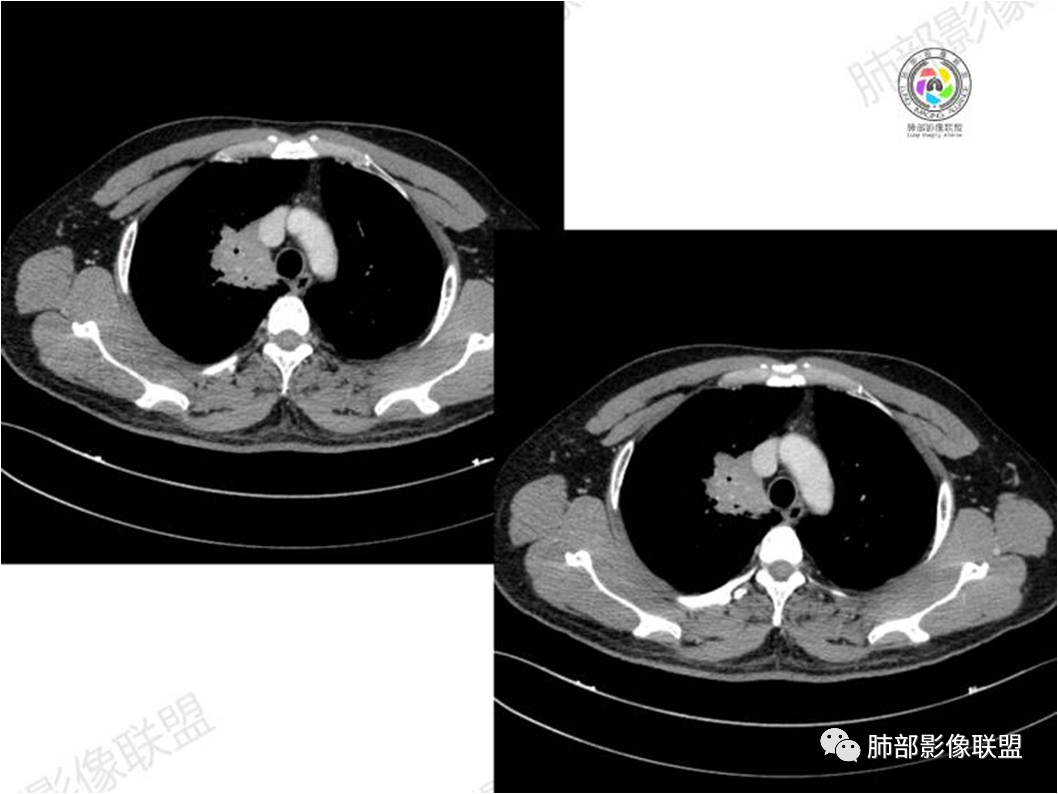

胸部CT:

中年男性,偶有咳嗽,右肺上叶近纵膈旁占位,内可见僵硬的支气管和小空泡征,病灶边缘可见分叶,毛刺,增强病灶中度以上不均匀强化,可见血管造影征,考虑恶性病变,腺癌可能性大。

右肺上叶纵隔胸膜侧一实性肿块,与纵隔胸膜宽基底相连,局部脂肪间隙消失,形态欠规则,内部可见多个小空泡,平扫密度尚均匀,增强后可见点条状强化,内部穿行血管,周围肺组织干净,纵隔淋巴结略肿大,男性44岁,只有咳嗽,考虑恶性肿瘤,腺癌,鳞癌。鉴别结核,OP,炎性假瘤。

右肺上叶近纵膈旁肿块,密度均匀,边缘分叶,毛刺,气管受压变窄,不均匀强化,可见血管造影征,考虑淋巴瘤,鉴别炎性假瘤。

中年男性,右肺上叶纵隔旁软组织肿块,边缘膨隆、毛糙,可见多发分叶,支气管穿行,部分截断,增强后密度欠均匀,纵隔内见多发小淋巴结,首先考虑恶性,腺癌,鉴别淋巴瘤

中年男性,右肺上叶纵隔旁肿瘤,稍膨隆,有毛刺,支气管穿行,远端闭塞,强化均匀,血管走行尚可,考虑淋巴瘤可能性大(支气管远端闭塞,不太符合),鉴别腺癌(气管穿行后闭塞,不太符合),op(病灶稍膨隆)

患者中年男性,咳嗽就诊,无其他不适。胸部CT:右肺上叶尖段上纵膈旁肿块,边界清楚,边缘光滑,内见支气管受压变窄,伴阻塞性改变,增强均匀强化,见血管造影征。综合考虑恶性病变,小细胞肺癌或淋巴瘤。气管镜活检应能明确。

中年男性,右肺上叶纵隔旁实性病灶,边缘有彭隆,有平直,有分叶,有尖角,病灶边缘中心可见支气管征,周围少许磨玻璃,边缘模糊,增强后动脉期病灶可见强化血管影,渐进性强化,临近血管界限清晰。考虑炎性病灶,普通炎性肉芽肿?结核?炎性肌纤维母细胞瘤?鉴别腺癌,淋巴瘤